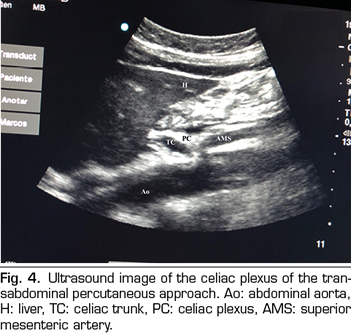

PERCUTANEOUS ULTRASOUND-GUIDED CELIAC PLEXUS NEUROLYSIS

In recent years, ultrasound has made head against fluoroscopy and CT in interventional pain management. The first describing the technique on the celiac plexus was Bhatnagar (31), and it could be performed percutaneously at the patient’s bedside and supine, which gives greater comfort for both the patient and the doctor. However, there are still no randomized controlled trials comparing abdominal ultrasound neurolysis of the celiac plexus versus opioid systemic treatment. The technique is performed using a convex transducer (2-5 MHz), initially placed just below the xiphoid process in the transverse plane, to identify structures, such as liver, stomach, intestine, portal veins, cava and aorta. With the help of the Doppler, we scanned caudally to identify the bifurcation of the celiac trunk in the hepatic and splenic arteries, and more distally in the superior mesenteric artery. Then we rotate the transducer in the longitudinal plane, visualizing in the same image the bifurcation of the aorta in the celiac trunk and in the superior mesenteric artery with the celiac plexus surrounding these structures. The approach is performed in plane, transabdominal, through the liver or stomach, as long as there are no large vessels interfering with the needle path (Figure 4).